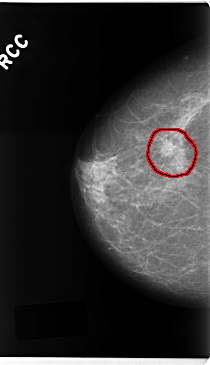

ics_version 1.0 filename C-0225-1 DATE_OF_STUDY 19 3 1997 PATIENT_AGE 55 FILM FILM_TYPE REGULAR DENSITY 2 DATE_DIGITIZED 14 4 1998 DIGITIZER LUMISYS LASER SEQUENCE LEFT_CC LINES 4744 PIXELS_PER_LINE 2512 BITS_PER_PIXEL 12 RESOLUTION 50 NON_OVERLAY LEFT_MLO LINES 4744 PIXELS_PER_LINE 2696 BITS_PER_PIXEL 12 RESOLUTION 50 NON_OVERLAY RIGHT_CC LINES 4736 PIXELS_PER_LINE 2728 BITS_PER_PIXEL 12 RESOLUTION 50 OVERLAY RIGHT_MLO LINES 4736 PIXELS_PER_LINE 2712 BITS_PER_PIXEL 12 RESOLUTION 50 OVERLAY |

FILE: C_0225_1.RIGHT_CC.OVERLAY TOTAL_ABNORMALITIES 1 ABNORMALITY 1 LESION_TYPE MASS SHAPE OVAL MARGINS SPICULATED ASSESSMENT 5 SUBTLETY 5 PATHOLOGY MALIGNANT TOTAL_OUTLINES 1 BOUNDARY |